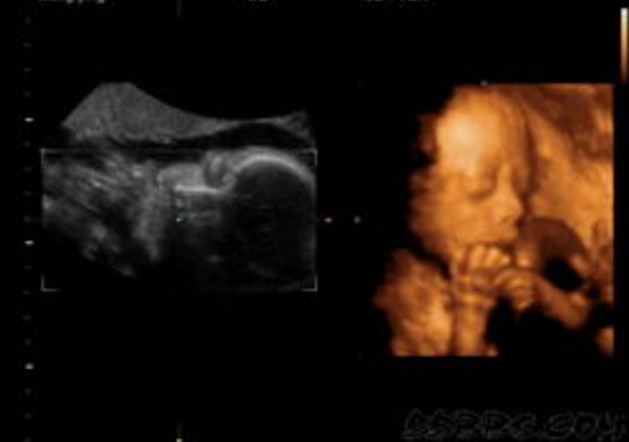

30岁的小孙就有唇裂,修补过的疤痕仍很分明。在最近一次三维B超显示,腹中的胎儿居然中度唇裂。她通知大夫,由于她诞生就有唇裂,小时老是被讪笑和厌弃。所有,无论怎样也要流掉腹中的宝宝,她不想让她的孩子再经历这样的经历。

大夫却通知小孙,现在已经孕21周,如果引产对身材损伤十分大,如果在次怀孕,不能包证就不会得唇腭裂,第二次仍会怀上唇腭裂宝宝的几率约为4%,假如怀过两次唇腭裂的宝宝,第三次怀上唇腭裂宝宝的几率会提升到14%。如今婴儿唇腭裂整形手艺,已经十分告捷,即使是重度的唇腭裂,仍是能够修补得简直看不出来了。倡议把孩子生上去,不要由于这点瑕疵,就将宝宝的性命闭幕。